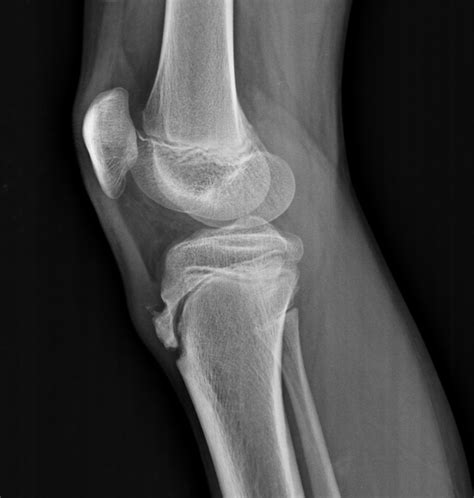

The primary purpose of an Osgood Schlatter X ray is not necessarily to "diagnose" the condition, as that is primarily a clinical diagnosis, but rather to look for specific findings that confirm the stress at the insertion point of the patellar tendon. When reviewing these images, medical professionals look for:

• Soft tissue swelling: Visible inflammation around the patellar tendon.

• Fragmentation: In more chronic or severe cases, the X-ray may show small bony fragments pulling away from the tibial tubercle.

• Irregularity: The surface of the bone may appear rough or jagged rather than smooth.

• Rule-out conditions: It is crucial to ensure the pain is not caused by bone tumors, fractures, or infections, which may present similarly.

If your doctor requests an Osgood Schlatter X ray, you should not be concerned. It is a quick, painless, and low-radiation diagnostic procedure. Typically, the technician will take images from a few different angles, most notably a lateral (side) view of the knee, to get a clear picture of the tibial tubercle.